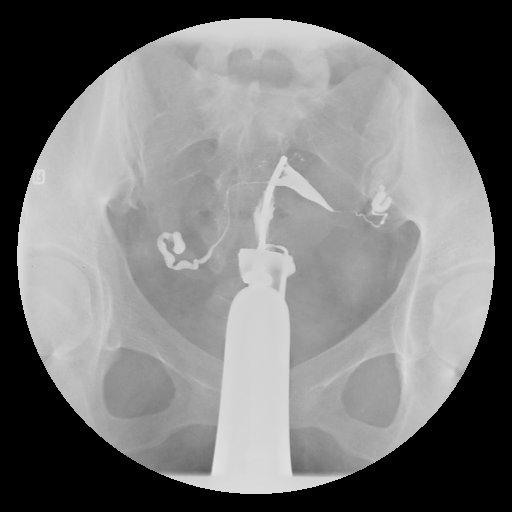

顯影劑滯留於雙側輸卵管周圍-骨盆腔沾黏

顯影劑滯留於雙側輸卵管周圍-骨盆腔沾黏示意圖